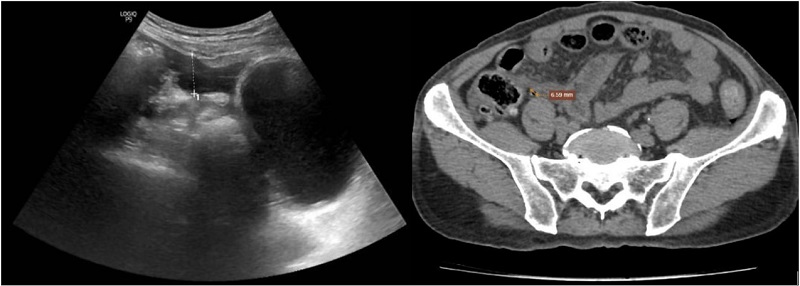

Kết quả siêu âm (bên trái) và chụp CT (bên phải) đều cho hình ảnh nghi ngờ thủng tạng rỗng

Kết quả chẩn đoán hình ảnh ghi nhận: Chụp X-quang có dấu hiệu liềm hơi dưới cơ hoành hai bên; Siêu âm có khí tự do ổ bụng, nghi thủng tạng rỗng vùng hành tá tràng; CT scanner ghi nhận nhiều dịch và khí tự do trong ổ bụng, hướng tới thủng tạng rỗng.